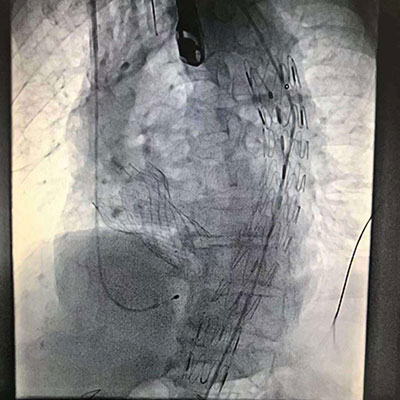

TAVR+TEVAR 影像

大会首日,我院血管病诊疗中心主任罗建方教授率领心脏瓣膜介入多学科团队进行了经导管主动脉瓣置换术联合胸主动脉腔内修复术(TAVR plus TEVAR)的手术直播。据悉,这例一站式经股动脉路径TAVR+TEVAR治疗重度主动脉瓣狭窄合并胸主动脉穿透性溃疡的术式在国际上尚未见报道。术前心脏瓣膜介入多学科团队在查阅国内外文献基础上,对TAVR及TEVAR常见并发症(脑卒中、冠脉堵塞、传导阻滞、脊髓缺血等)的风险进行全面评估,对TAVR及TEVAR的先后顺序进行充分讨论。本次手术虽只用了1个多小时,在整个过程中,心脏团队成员默契配合,以精湛的技术赢得了与会同行的一致赞誉。